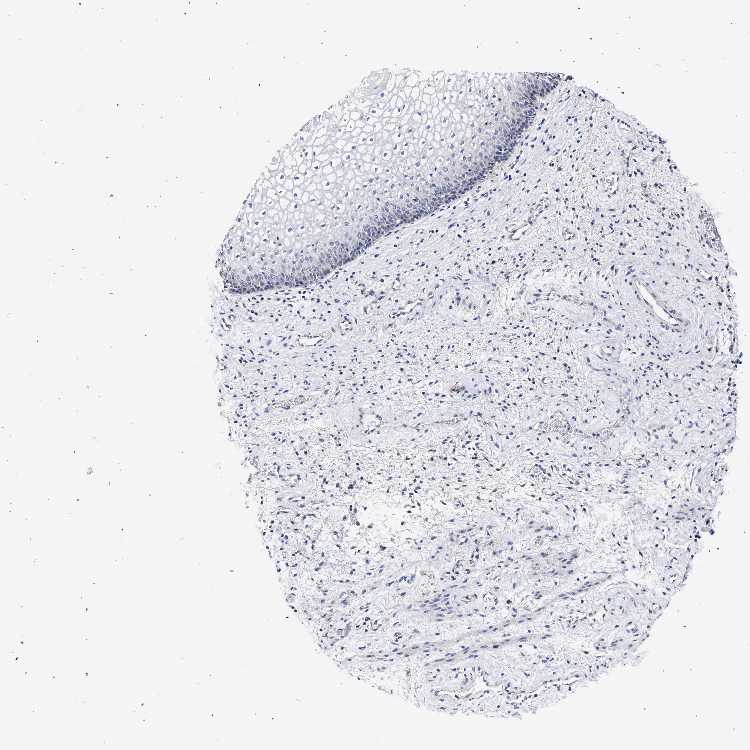

VAGINA - Antibody stainingi

Antibody staining in the annotated cell types in the current human tissue is reported as not detected, low, medium, or high, based on conventional immunohistochemistry profiling in selected tissues. This score is based on the combination of the staining intensity and fraction of stained cells.

Each image is clickable and will lead to virtual microscopy that enables deeper exploration of all samples and also displays staining intensity scores, fraction scores and subcellular localization as well as patient and tissue information for each sample.

Antibody HPA021261Antibody HPA021325

Squamous epithelial cells Not detectedNot detected